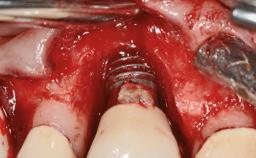

A 77-year-old male patient was referred for the management of frequent and repeated acrylic fracture of his existing mandibular fixed full-arch implant-supported metal/acrylic prosthesis. He also complained about softtissue soreness and the lack of retention and stability of his maxillary removable partial metal/acrylic prosthesis. Both prostheses had been delivered two years previously as part of his full-mouth rehabilitation (caries, tooth wear, tooth fracture). His medical history revealed high blood pressure, controlled with the use of antihypertensive medication.

Defining Characteristics Fully edentulous lower jaw to be rehabilitated with two or more implants

Modality > 4 implants, extending to mental nerve region

Bone Volume Horizontally and vertically sufficient